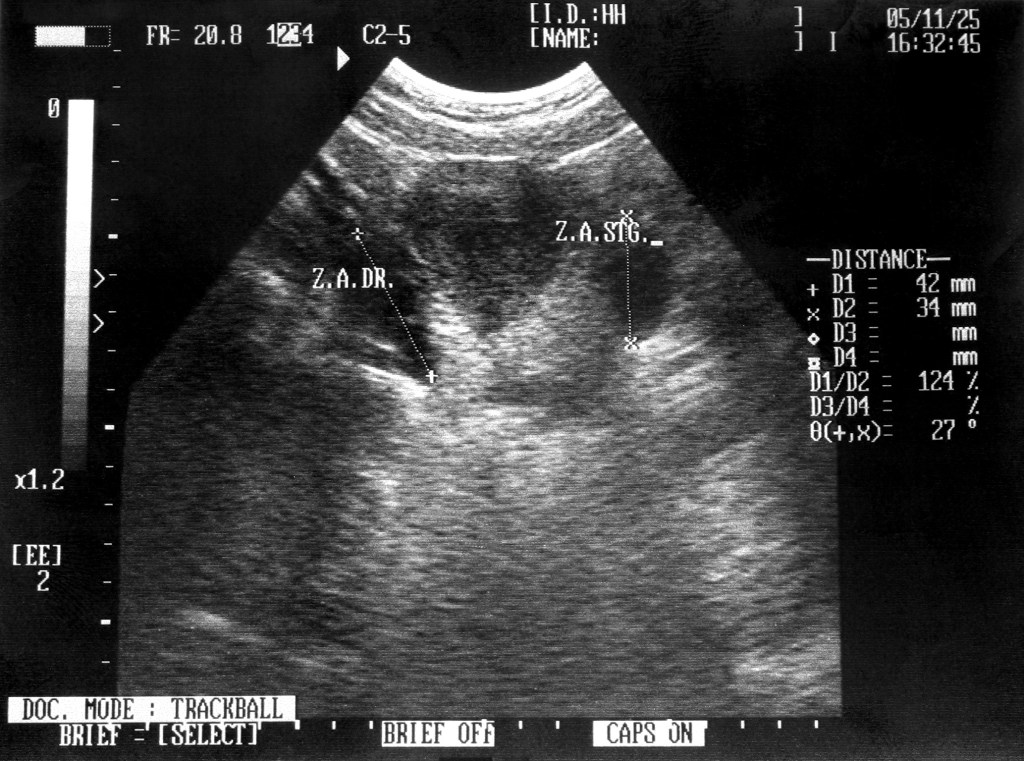

- Acortamiento del cuello del útero o incompetencia cervical: se acorta y dilata antes de tiempo.